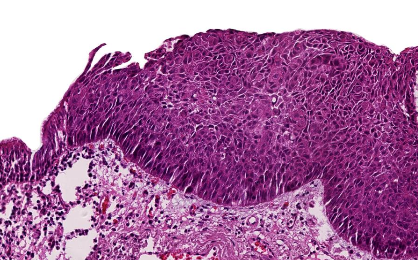

Carcinoma de células escamosas

Característica morfológica macroscópica de los carcinomas de células escamosas

Tumores grandes con hemorragia y necrosis

Característica en cuanto al crecimiento de carcinoma de células escamosas

Crecimiento central exofítico endobronquial